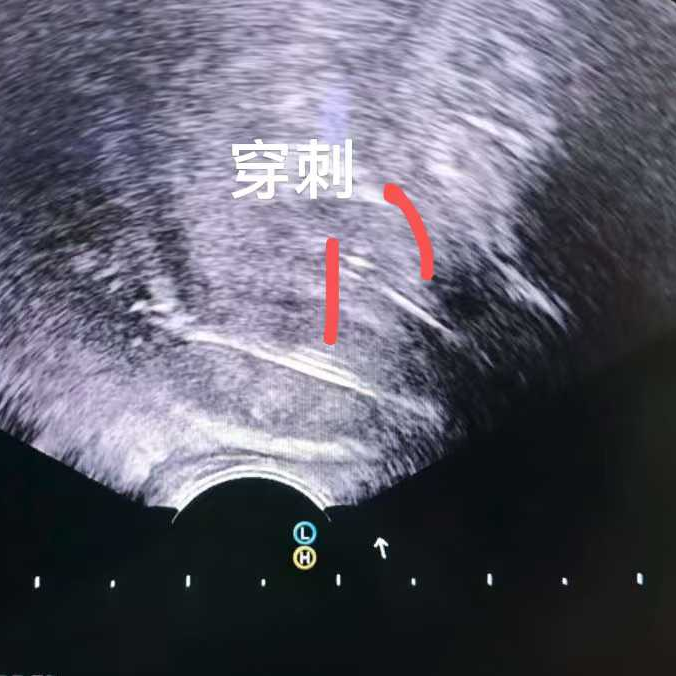

比如這位馬來西亞患者,PSA指標正常,但影像卻發(fā)現(xiàn)可疑病灶,結(jié)果穿刺證實是少見的前列腺尿路上皮癌,在我院接受了冷凍消融治療。

換句話而言,PSA能夠很好地預測前列腺癌的可能性,但是畢竟不是金標準。確診前列腺癌必須輔以病理診斷。

這也讓多數(shù)患者提出疑問:我復查PSA都正常了,為什么還要做穿刺?這里給大家分享我國《中國臨床腫瘤學會(CSCO)前列腺癌診療指南2025》中推薦的前列腺初次穿刺指征: